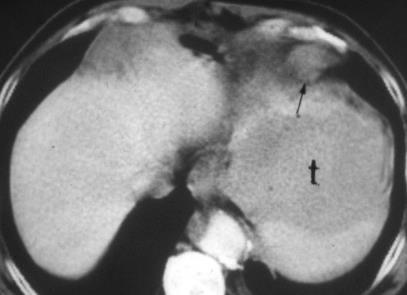

Mesotelioma epitelioide

Postmortem. 318 pacientes.

Diseminación extratorácica. 55,4%

Hígado. 31,9%

Bazo. 10.8%

Tiroides. 6,9%

Cerebro. 3%.

“Enfermedad Intersticial pulmonar” 0,6%

Kato K. et al. HRCT Findings of Asbestosis Revisited; Radiologic and Pathologic Correlations. Exhibit. RSNA 2012/ / Karpathiou G et al. Pleural neoplastic pathology. Respiratory Medicine 2015